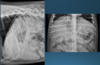

What is shown in these images?

*generalized hepatomegaly:

-extends past costal arch

-gastric axis no longer parallel with ribs; pylorus pushed caudal